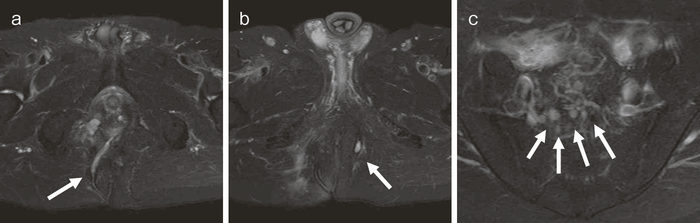

2. その他画像診断

内視鏡以外の画像診断には,超音波検査,CT検査,MRI検査などがあるが,CD関連腫瘍に関する診断は,やはり未確立である4)。こうしたcross sectional imagingにおいては,CDの炎症による腫瘤や膿瘍との鑑別が課題となる5)。CD関連消化管癌では病変が房状を呈することがあるが(図27),早期の病変を診断することは困難である。臨床では,痔瘻や肛門周囲膿瘍の評価のためのcross sectional imagingによる検査でCD関連消化管癌の可能性がある所見を拾い上げられるかがポイントとなるが,確定診断後に画像診断所見を見直した際に,所見に気付くことも少なくない。また確定診断のためには,内視鏡検査による生検や外科的な生検か細胞診を行う必要がある。

図27 CD直腸肛門部癌の骨盤造影MRI検査像

直腸内に増強効果を受ける分葉状の腫瘤を認める。